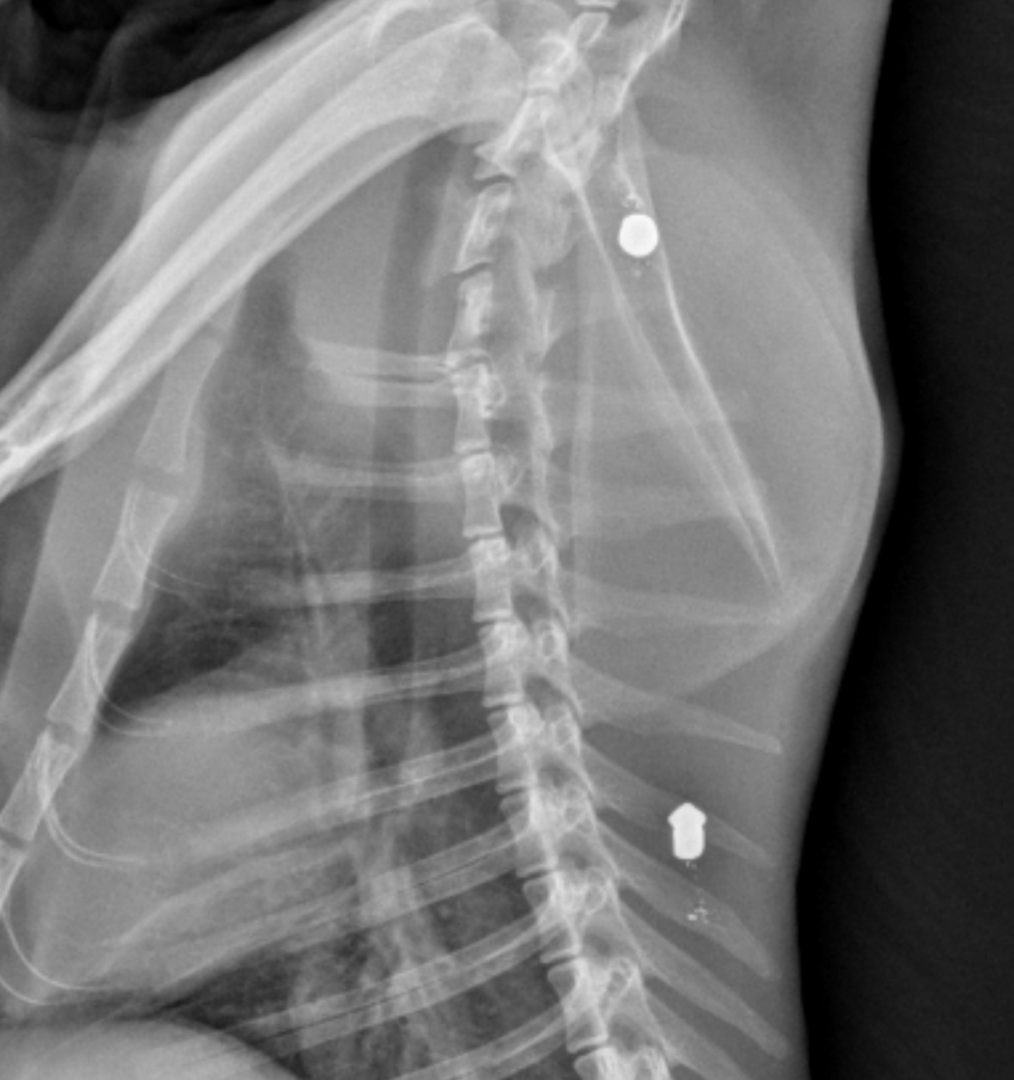

Las radiografías realizadas al animal confirmaron la presencia de dos proyectiles compatibles con perdigones, lo que apunta a un acto intencionado de violencia contra los animales

Las radiografías realizadas al animal confirmaron la presencia de dos proyectiles compatibles con perdigones, lo que apunta a un acto intencionado de violencia contra los animales. El caso ha sido hecho público por personas voluntarias dedicadas a la protección y cuidado de colonias felinas en Fraga, que alertan de la gravedad de lo ocurrido y de la vulnerabilidad de estos animales.